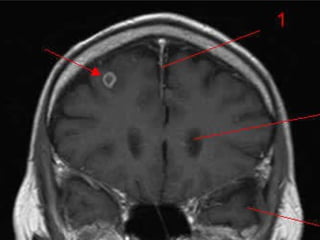

Au niveau du système nerveux La cysticercose atteint essentiellement le système nerveux central .  Le tissu nerveux oppose une réaction inflammatoire à l’infection qui, associée à la dégénérescence de la larve,  marque le début des signes neurologiques,  alors que la larve vivante reste cliniquement silencieuse.

Quatre localisations anatomiques sont décrites :   -  parenchymateuses  : les kystes habituellement inférieurs à 1 cm de diamètre, sont localisées dans les hémisphères cérébraux, c’est l’atteinte la plus fréquente, plus de 60% des patients

Au niveau dusystème nerveux La cysticercose atteint essentiellement le système nerveux central . Le tissu nerveux oppose une réaction inflammatoire à l’infection qui, associée à la dégénérescence de la larve, marque le début des signes neurologiques, alors que la larve vivante reste cliniquement silencieuse.

Quatre localisations anatomiquessont décrites : - parenchymateuses  : les kystes habituellement inférieurs à 1 cm de diamètre, sont localisées dans les hémisphères cérébraux, c’est l’atteinte la plus fréquente, plus de 60% des patients